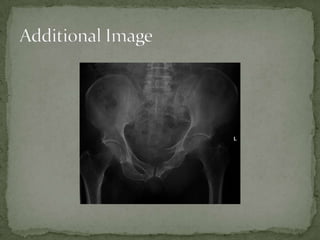

A 33-year-old male construction worker presented with extreme pain in his right pelvis and lower back after falling 20 feet from scaffolding and landing on his fully extended right leg. He was tachycardic and diaphoretic. Examination found his right leg shortened with pain on range of motion and blood at the urethral meatus. Imaging revealed significant hemorrhage into the retroperitoneum likely from branches of the internal iliac artery, superior gluteal artery, or sacral venous plexus. He received intravenous fluids, oxygen, and a trauma workup. An orthopedic consult was emergently placed for possible unstable pelvic fractures requiring angiography.